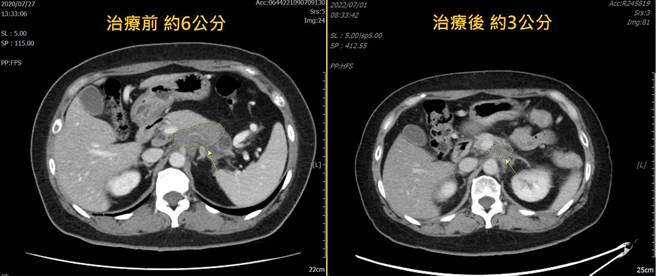

锺智渊表示,病患3年前癌症指数(CA199)由原本超标1587U/ml降到目前9.1U/ml,另外,胰臟癌肿瘤从3年前约6公分,现在也缩小为3公分。病患3年前约80公斤,体重一口气掉了20公斤,食欲、精神体力各方面不佳。先完成两个月放射线治疗后,精神已有改善,接续接受化学治疗,疾病稳定控制,病人体重已由原本最低60公斤,逐渐增加至70公斤,饮食、精神各方面良好,生活恢復日常。